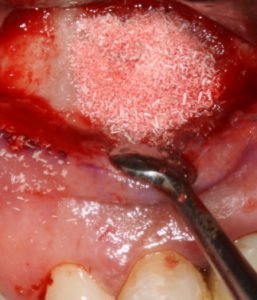

Figura 3: enxerto realizado